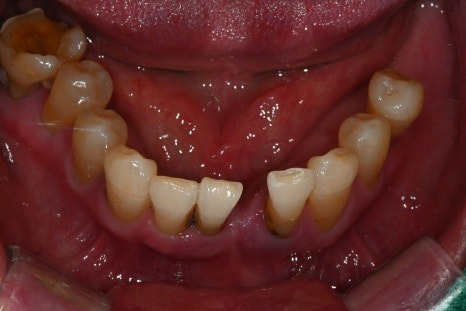

· 상악은 잇몸뼈가 매우 얇고 치아가 거의 남아 있지 않은 상태

· 하악은 부분 결손과 앞니의 심한 동요

· 식사가 어려울 정도로 기능 저하가 심한 상태

치료 계획 및 수술 과정

이 환자분은 다음과 같은 계획으로

치료를 진행했습니다.

· 수면마취(의식하 진정요법) 하에 진행

· 상악 양측 상악동 거상술 + 임플란트 10개 식립

· 하악 발치 후 결손 부위 포함 임플란트 6개 식립